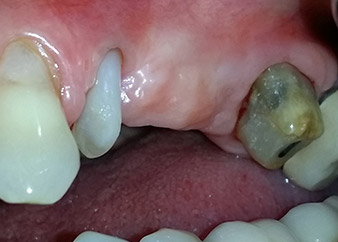

Eine 58-jährige Patientin, die auch eine gute Freundin und ärztliche Kollegin ist, beschwerte sich über Schmerzen und erhöhte Beweglichkeit ihres Brückenpfeilers 24. Es lag auch eine parodontale Entzündung vor, mit Taschentiefen von 7 mm mesiobukkal und mehr als 12 mm distal und einer Furkationsbeteiligung dritten Grades. Darüber hinaus zeigte die Röntgenaufnahme eine großflächige apikale Aufhellung am endodontisch (alio loco) vorbehandelten Zahn 24 (Abb. 1).

Ein Jahr zuvor waren die Zähne 25 und 26 vor dem Einsetzen der Brücke aufgrund traumatischer und endoparodontaler Ursachen extrahiert worden. Eine Paro-Endo-Läsion wurde bei unklarer ätiologischer Hauptkomponente für den Zahn 24 diagnostiziert. Die Patientin machte deutlich, dass sie ihre Pfeilerzähne 24 und 27 behalten und keinen endgültigen oder temporären herausnehmbaren Zahnersatz akzeptieren will. Darum wurde vereinbart, alles zu versuchen, beide Zähne, trotz der nach den radiologischen und klinischen Befunden als schlecht einzustufenden Prognose, zu erhalten.

Außerdem wurde die Platzierung zweier verdeckt einheilender Implantate an den Positionen 25 und 26 bei einem chirurgischen Eingriff mit offenem parodontalen Debridement und Wurzelspitzenresektion am Zahn 24 geplant. Aufgrund des vertikalen Knochendefizits im Implantationsbereich wurde auch eine interne Sinusbodenaugmentation geplant.

Nach einer lokalen Applikation von 25-prozentigem Metronidazol-Gel (Elyzol) in die Taschen des Zahns 24 wurde die ursächliche Behandlung mit systematischer Parodontaltherapie einschließlich Full-Mouth-Disinfection begonnen. Die orthograde Wurzelkanalbehandlung wurde mittels einer thermoplastischen Obturation mit Guttapercha, einem Glasfaserstift und einem Komposit-Stumpfaufbau revidiert (Abb. 2). Die Brücke wurde außer Okklusion wieder befestigt, um die ungestörte Heilung der GTR- und GBR-Bereiche zu gewährleisten.